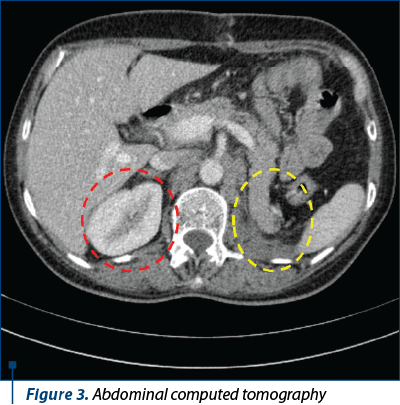

A computed tomography (CT) scan with intravenous contrast revealed a solid mass with malignant features located on the left kidney, multiple enlarged lymph nodes, and pulmonary metastases – cT3N1M1(pul) (Figures 1 and 2). The patient underwent radical left nephrectomy and para-aortic lymphadenectomy on January 17, 2018 (Figure 3). The pathologic study revealed papillary renal cell carcinoma (pT4pN1M1pul,lym) with subsequent immunohistochemical (IHC) results, as follows: PAX8 (+), vimentin (+), CD10 (+), AMACR (+), WT1 (-), calretinin (-).

Figure 3. Abdominal computed tomography